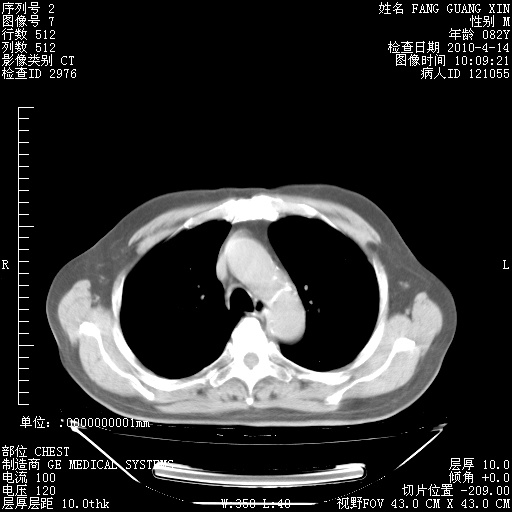

肺部CT平扫未见异常。

4月14日肺部CT